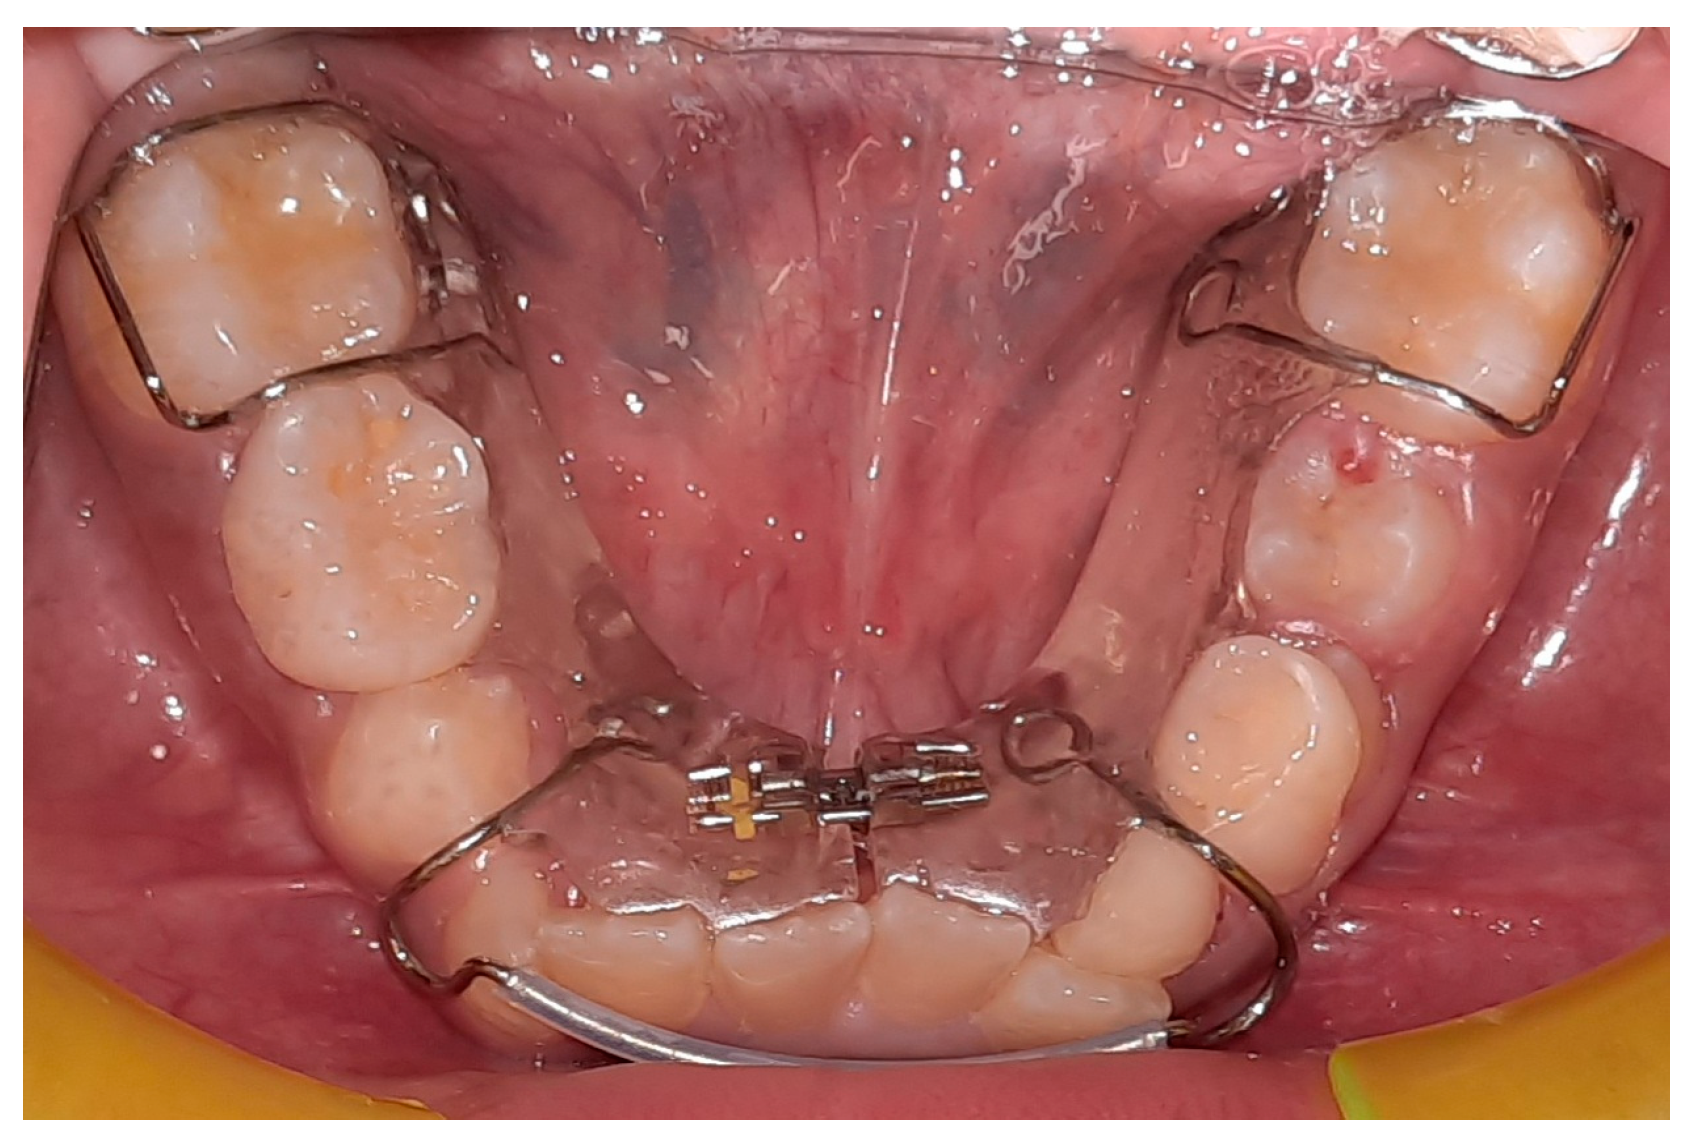

The lower jaw is considered the guiding arch in crowding therapy because it is difficult to modify its perimeter due to the more compact bone structure and the continuity with the mandibular branch, which does not allow for distalization [37,41]. In addition, the symphysis cartilage ossifies in the first year of life, so it is not possible to perform an orthopedic bone expansion, as in the upper jaw, working at the level of the median palatine suture [41,42]. The modalities of space recovery in mixed dentition are: arch perimeter increment, reduction in mesiodistal widths of teeth and serial extractions [2,43,44]. In the upper arch, the expansions are quite stable, but inferiorly, it is universally recognized that the expansion of the intercanine diameter always recurs, whereas expansion at the molar level is quite stable, which should be considered [27,45,46,47]. The space that can be recovered in the lower arch depends on the type of sector: in general, in the posterior sector, utilizing a lip bumper-style device, it is possible to recover a maximum of 2 mm of space per molar distalization in the posterior regions. At the molar level in the lateral sectors, the arch length could increase by about 0.4 mm; at the canine level, the arch length increases about 0.7 mm [48]. The vestibularization of one millimeter of the incisal margin in the anterior sector results in the gain of one millimeter of arch space, or roughly a ratio of one to one (changing the arch form) [47]. Schwarz’s appliance (Figure 3) and lip bumper (Figure 4) are two commonly used appliances for increasing lower dental arch dimensions [49]. In their study, Vincenzo Quinzi et al. compared the effects of these appliances on reducing mandibular crowding by increasing lower arch dimensions [27]. The study included twenty subjects (10 males and 10 females). Ten patients were treated with Schwarz’s appliance, and ten with lip bumper. The Schwarz appliance was more effective in increasing intercanine arch dimensions and arch perimeter, although the lip bumper reached a greater increase in arch length [27]. Since the 1970s, there have been reports of spontaneous changes in mandibular dentition caused by maxillary expansion [31,50]. Di Ventura et al. assessed the consequences of rapid maxillary expansion (RME) anchored to primary molars on the mandibular arch. A total of 54 patients were recruited for this study and divided into two groups: a test group (21 patients, 7.4 ± 1.2 years) who underwent RME, and a control group (17 patients, 7.3 ± 1.1 years old) who did not receive any treatment. The results of this study showed a significant increase in interdental width in the lower arch after 9 months of RME therapy [31]. Olivia Griswold et al. evaluated the changes in sagittal mandibular incisors’ position in response to lip bumper therapy using CBCT [32]. In this study, the authors compared a group that was treated only with rapid maxillary expansion (experimental group) and an RME + LB (lip bumper) group (control group) [32]. The CBCTs were placed in 3D on the mandibular structure, and the angular and linear alterations in the mandibular incisors throughout LB therapy were assessed. In the investigation, there was no statistically significant difference in the degree of mandibular incisor protrusion between the two groups; the lip bumper did not generate substantial proclination, protrusion or extrusion of the mandibular incisors. [13]. Air-rotor stripping (ARS) (Figure 5) is a technique for creating space during the mixed dentition period by reducing interproximal enamel thickness. Yahya B. Nakhjavani et al. assessed the efficacy of the mesial stripping of mandibular deciduous canines for the correction of rotated and lingually erupted lateral incisors in 42 patients with <3 mm mandibular crowding [33]. In this study, the mesial stripping of mandibular primary canines resulted in full crowding correction; in just few cases, the amount of crowding did not reach zero, and a small crowding in the range of 0.06 to 0.1 mm remained [33]. The extraction of all the first premolars with subsequent orthodontic treatment is the most used method to relieve dental crowding [51]. The importance and timing of extraction as a component of orthodontic therapy for late incisor crowding have been well investigated [35]. No difference in late incisor crowding is shown by the data, regardless of whether serial extraction or early or late premolar extraction is performed prior to orthodontic treatment. Additionally, selecting a non-extraction orthodontic procedure has been linked to post-retention crowding [35]. Maurits Persson et al. investigated changes in the mandibular incisor area from early adolescence to late adulthood in patients with a class I crowding malocclusion treated in the mixed dentition by the extraction of all first premolars without subsequent orthodontic treatment [35]. The extraction group included 24 subjects who had all their first premolars extracted at a mean age of about 11.5 years to treat a class I space deficiency malocclusion. The control group included 21 subjects who had normal occlusions at the age of 13 years [35]. The extraction group showed no improvements in lower incisor irregularity, and a significant increase in lower tooth space insufficiency into adulthood. Lower incisor irregularity and space shortage developed significantly in the control group throughout late adulthood [35]. Premolar extraction is the sole treatment option for severe crowding in a class I occlusion, allowing for spontaneous adjustments and more stable incisor alignment in late adulthood, according to the authors [35] (Table 2).

Figure 3. Schwarz’s appliance.